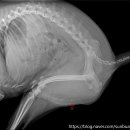

• 선부중앙동물의료센터 | 안산 고양이 이물 수술 전문 | 선부중앙동물의료센터 소화기 수술 후기 및 입원 관리

안녕하세요, 안산의 모든 반려가족분들! 선부중앙동물의료센터입니다. 🐾 고양이를 키우는 집사님들이라면 한 번쯤 '혹시 우리 아이가 이걸 먹은 건 아닐까?' 하는 걱정에 가슴이 철렁했던 적 있으실 거예요. 고양이는 호기심이 많고 혀의 돌기 때문에 이물질을 삼키기 쉬운 구조를 가지고 있거든요. 오늘은 소화기 이물...

환자들의 후기 등을 미리 살펴보는 것이 도움이 될 수 있습니다. ​ 다음으로, 병원의 시설과 장비 역시 중요한 고려 사항입니다. 최신 진단 장비(예: X-ray, 초음파, 혈액 검사 장비)를 갖추고 있는지, 수술실이나 입원실의 위생 상태는 어떠한지 등을 확인해야 합니다. 특히 응급 상황 발생 시 신속하고 정확한 진단과...